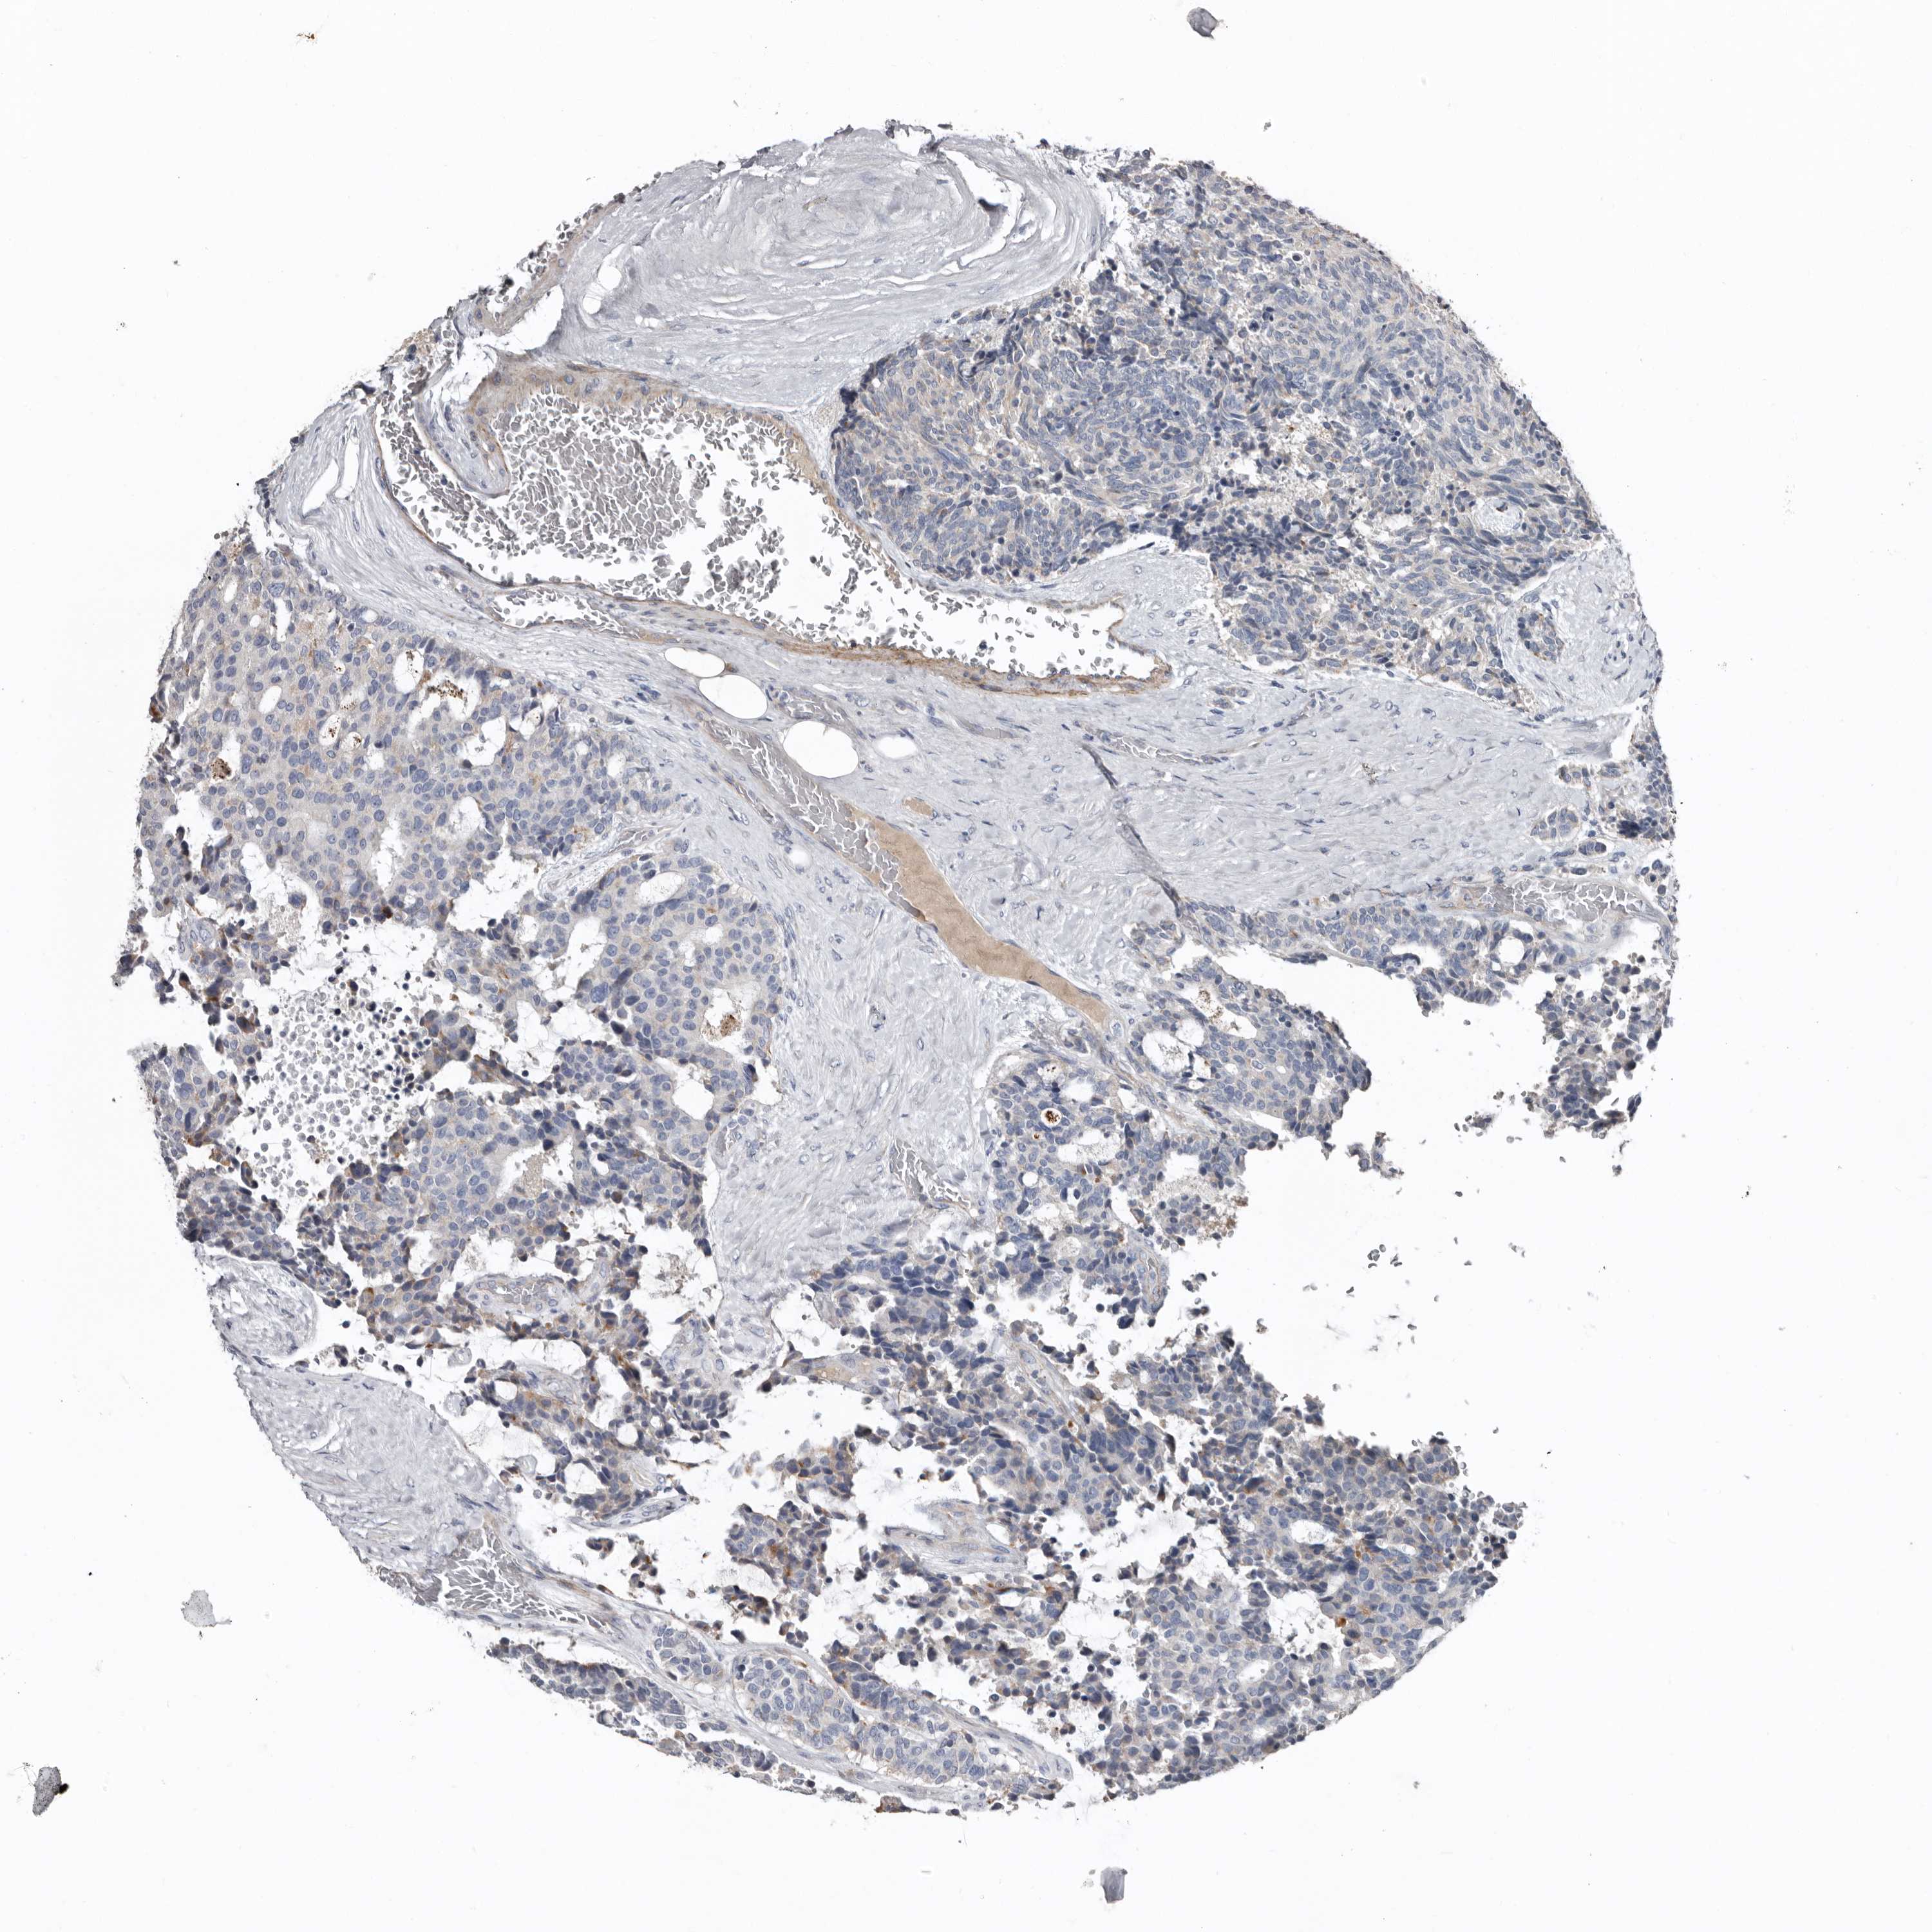

CARCINOID - Protein expressioni

A mouse-over function shows sample information and annotation data. Click on an image to view it in a full screen mode. Samples can be filtered based on level of antibody staining by selecting one or several of the following categories: high, medium, low and not detected. The assay and annotation is described here.

Antibody stainingi

Antibody staining in the annotated cell types in the current human tissue is reported as not detected, low, medium, or high, based on conventional immunohistochemistry profiling in selected tissues. This score is based on the combination of the staining intensity and fraction of stained cells.

Each image is clickable and will lead to virtual microscopy that enables deeper exploration of all samples and also displays staining intensity scores, fraction scores and subcellular localization as well as patient and tissue information for each sample.

Antibody HPA025019

Antibody HPA029553

Staining

High

Medium

Low

Not detected

Intensity

Strong

Moderate

Weak

Negative

Quantity

>75%

75%-25%

<25%

None

Location

Nuclear

Cytoplasmic/membranous

Cytoplasmic/membranous,nuclear

Carcinoid, malignant, NOS

Carcinoma, NOS